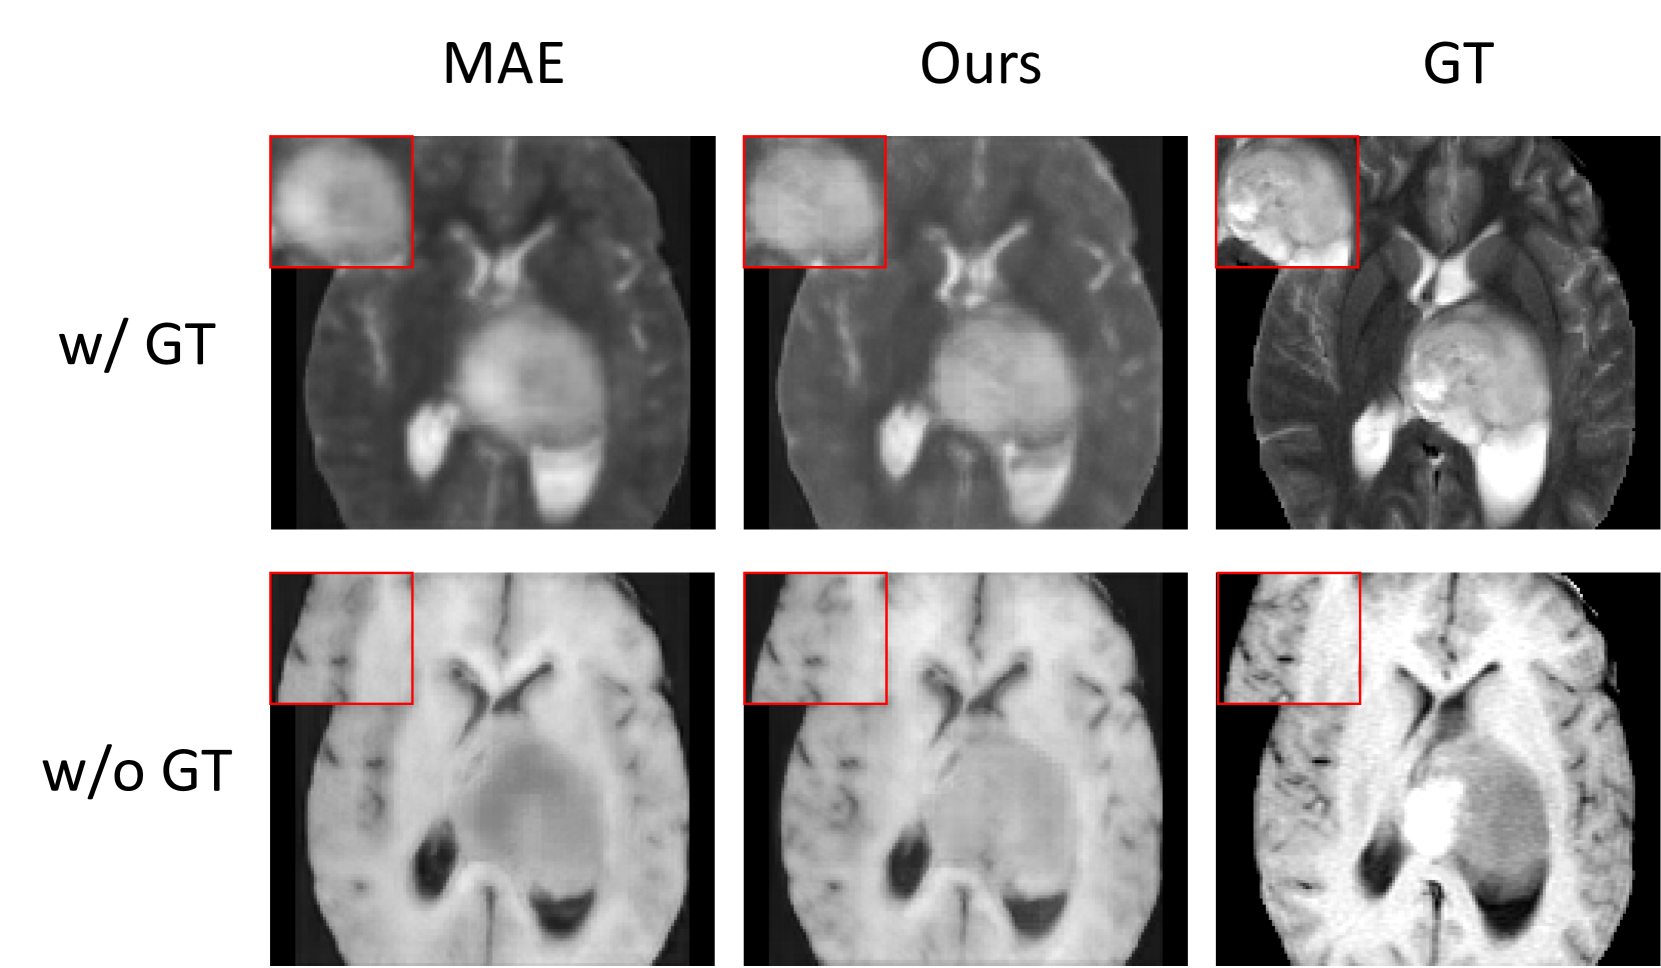

Figure 3: Visualization of reconstructed training modalities. Row 1 indicates that ground truth (GT) is available during pre-training, while row 2 means GT is absent. Column 1-3 represents vanilla multimodal MAE, ours, and GT.

Visual comparison of reconstructed modalities. Fig. 3 visually compares the reconstructed results before and after using our distribution approximation. The ground truth in the first row is available for self-supervision. After providing extra supervision by distribution approximation, the tumor area of reconstructed images is slightly clearer. This demonstrates that auxiliary supervision can encourage the pre-training process to focus more on tumor-aware reconstruction. From the second row where the ground truth is absent, we see that more brain anatomical details are recovered, proving effectiveness of auxiliary supervision.